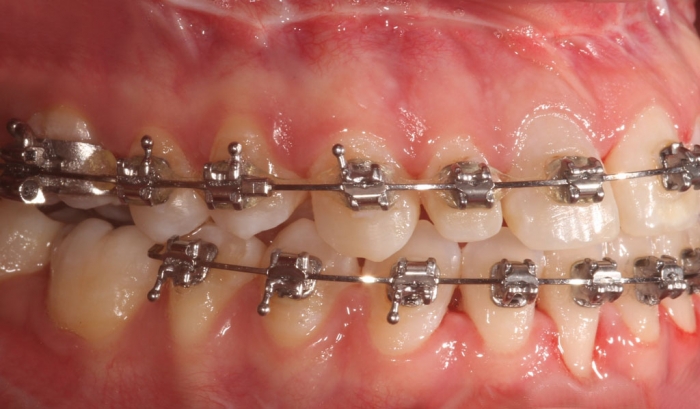

Mordida inicial - Clínica Cliniface

Mordida inicial